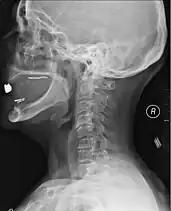

| Other names: Spinal trauma | |

![]() | |

| MRI of fractured and dislocated neck vertebra that is compressing the spinal cord | |

A radiographic evaluation using an X-ray, CT scan, or MRI can determine if there is damage to the spinal column and where it is located.[15] X-rays are commonly available[60] and can detect instability or misalignment of the spinal column, but do not give very detailed images and can miss injuries to the spinal cord or displacement of ligaments or disks that do not have accompanying spinal column damage.[15] Thus when X-ray findings are normal but SCI is still suspected due to pain or SCI symptoms, CT or MRI scans are used.[60] CT gives greater detail than X-rays, but exposes the patient to more radiation,[62] and it still does not give images of the spinal cord or ligaments; MRI shows body structures in the greatest detail.[15] Thus it is the standard for anyone who has neurological deficits found in SCI or is thought to have an unstable spinal column injury.[63]